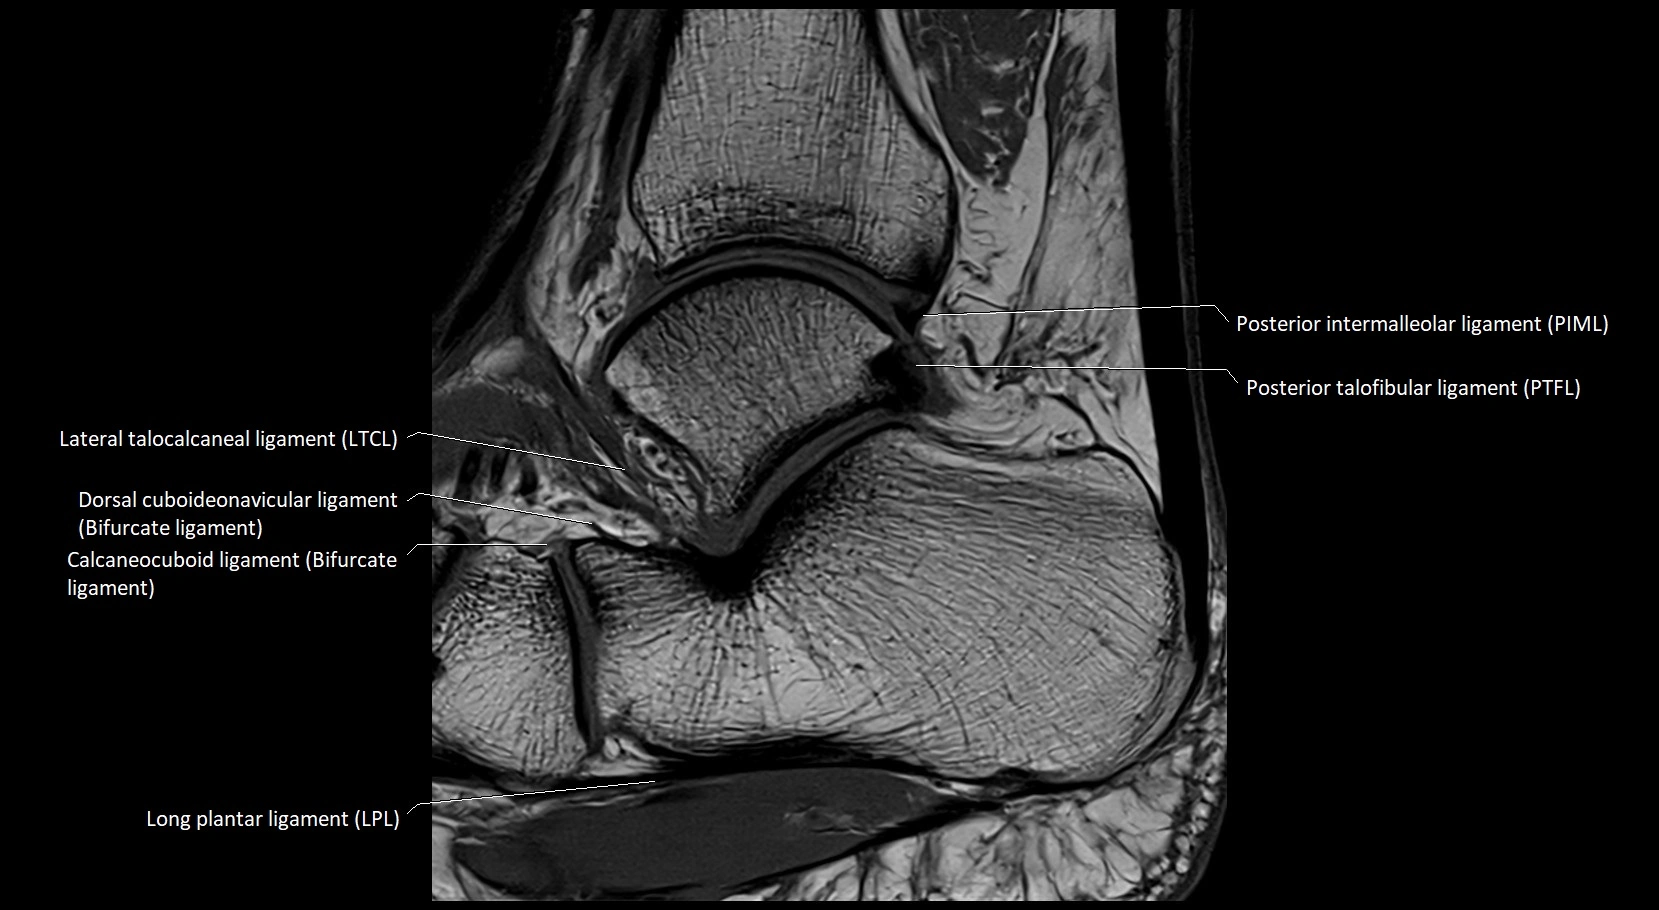

MRI image

image